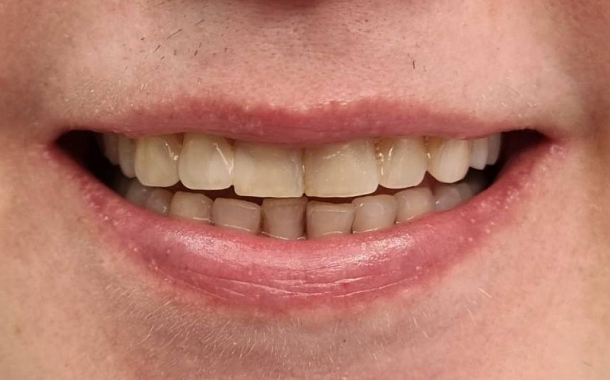

Полный прайс-листКейсы: до и после